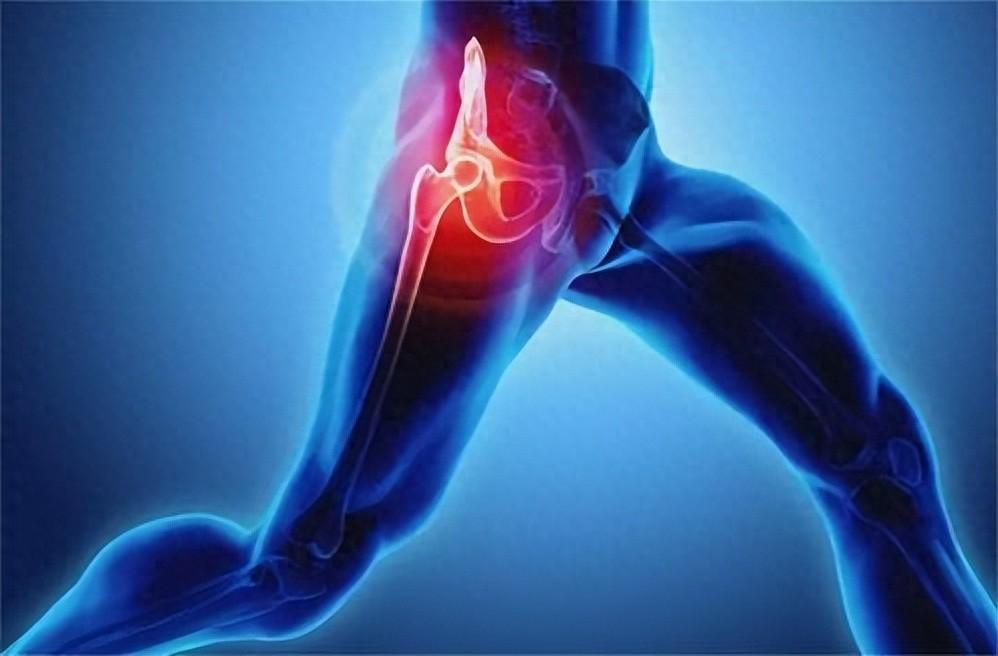

強化核心肌群

腰痛常與核心肌群無力有關。透過運動加強腹肌、背肌與骨盆底肌肉的力量,能穩定脊椎並減輕腰椎負擔。

維持脊椎正常曲度

久坐或姿勢不良容易造成腰椎曲度異常,進而引發腰痛。適度的伸展與肌力訓練,有助於矯正體態並維持正常的脊椎曲線。

促進軟組織修復

運動能刺激肌肉與關節周圍軟組織的新陳代謝,促進受損組織修復,同時增加關節靈活度,減少僵硬與疼痛感。